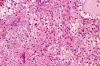

These photos were obtained from the formalin fixed paraffin embedded sections.